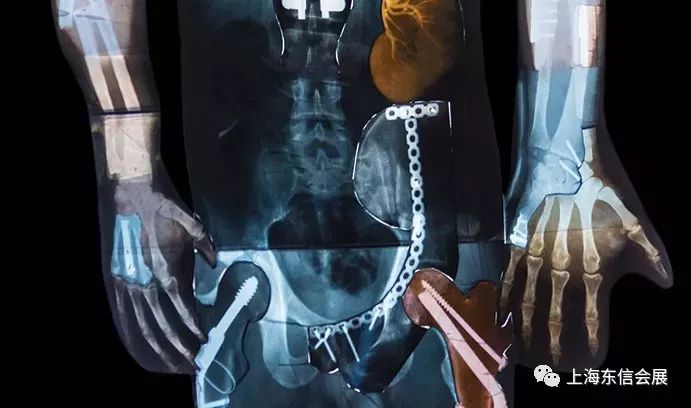

骨科类医疗器械产

依据 Evaluate Med Tech发布的报告,从市场来看,全球骨科市场上知名跨国公司占据绝对主导地位,主要包括强生、史赛克、捷迈、美敦力、辛迪思、施乐辉、巴奥米特等,其中美国公司以其先进的产品技术、管理体系,以及成熟的商业运作模式领先于全球同行。同时,通过并购运作,如强生收购辛迪思、捷迈收购巴奥米特、史赛克收购中国的创生控股有限公司、美致力收购康辉医疗器械有限公司,美国公司几乎占据骨科医疗器械行业 85% 以上的市场份额。

过去几年,全球骨科医疗器械市场份额增幅为5%左右,我国骨科医疗器械市场份额增幅超过20%,远远超过了其他国家的增长速度,并呈持续上升趋势。从近几年市场份额的演变情况分析,我国骨科医疗器械市场份额增幅较大,并将在较长时间内维持这一趋势,最终可能占据70%~80%的国内市场份额。目前,国内骨科植入器械企业已超过60家,整个行业处于比较分散的状态,估计未来会有更多的竞争者进人这一高增长领域,也会面临更多外企和跨国公司的竟争。因此,国内在这一行业需要进一步整合,龙头企业需进一步扩大市场份额。

(1)关节产品领域:2012年国内关节产品销售情况显示,跨国公司占64%的销售额,国内企业仅占36%,国内企业在国内市场占比尚有较大发展空间。目前,国内规模较大的厂商有北京市春立正达医疗器械股份有限公司、北京蒙太因医疗器械有限公司、北京百慕航材高科技股份有限公司、普鲁斯外科植人物(北京)有限公司等,与其竞争的外企或合资企业主要有史赛克、捷迈、强生、施乐辉等。

(2)脊柱产品领域:从国内关节产品销售收入情况来看,跨国公司约占61%的销售份额,而国内企业仅占39%。国内市场被外资企业主导,国内企业尚有较大的发展空间。国内规模较大的企业有威高集团有限公司、北京市春立正达医疗器械股份有限公司、欣荣医疗、康辉医疗、博尔特医疗等,与其竞争的外资企业主要有强生、美致力、史赛克等。

(3)创伤产品领域:国内企业和外资企业在市场销售份额上分别占57%和43%,在该领域,国内企业和外资企业势均力敌,国内市场未被外资企业主导。国内规模较大的企业有创生医疗器械(中国)有限公司、威高集团有限公司、欣荣医疗、康辉医疗、威曼医疗科技有限公司等,与其竞争的外资企业主要有辛迪思、施乐辉、强生、史赛克等。